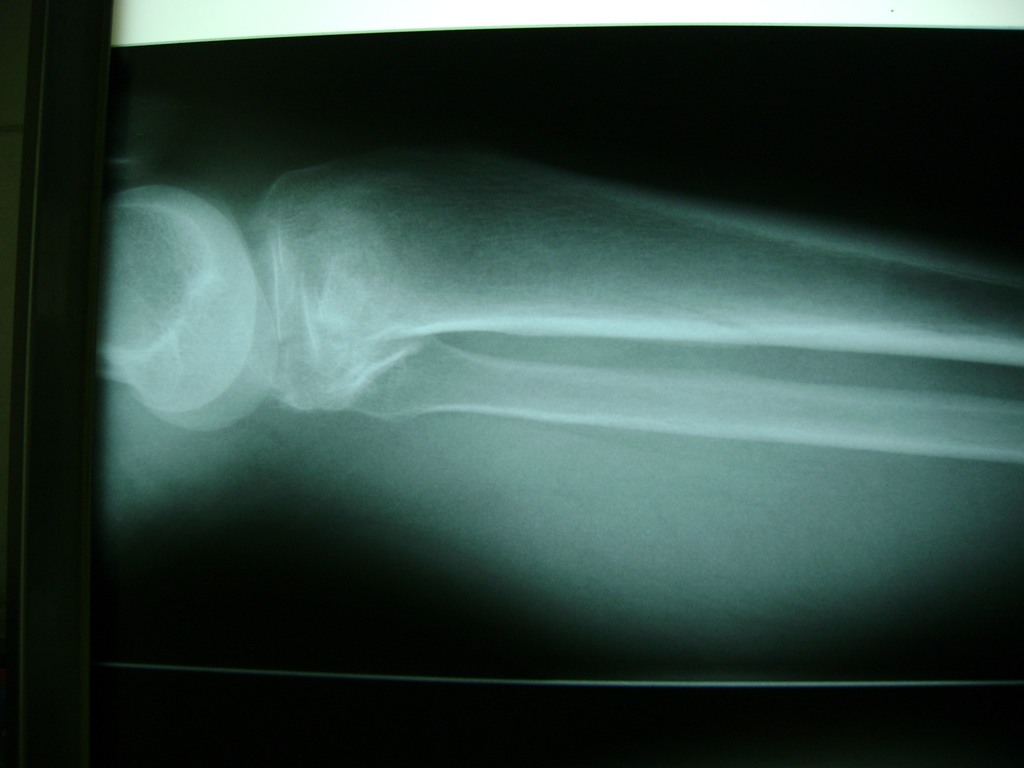

Fémur - Rodilla